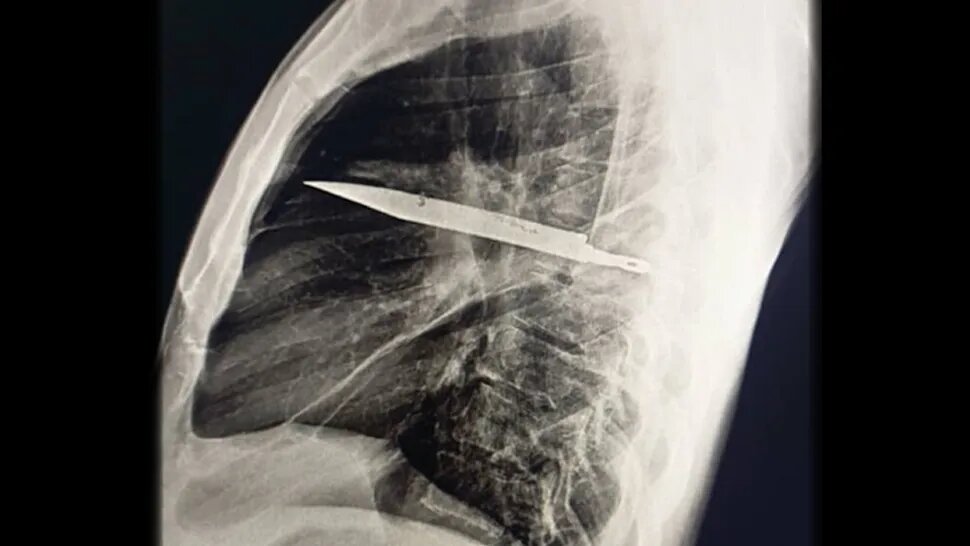

تصویربرداری با اشعه ایکس و سیتیاسکن نشان داد تیغهای بزرگ از چاقو از پشت قفسه سینه وارد شده، بین دندههای پنجم و ششم گیر کرده و نوک آن تا جلوی قفسه سینه بین دندههای سوم و چهارم امتداد یافته است. شکستگیهای ترمیمشده در استخوان کتف و چند دنده نیز مشاهده شد. همچنین اطراف تیغه، بافت مرده و چرک تجمع یافته بود.